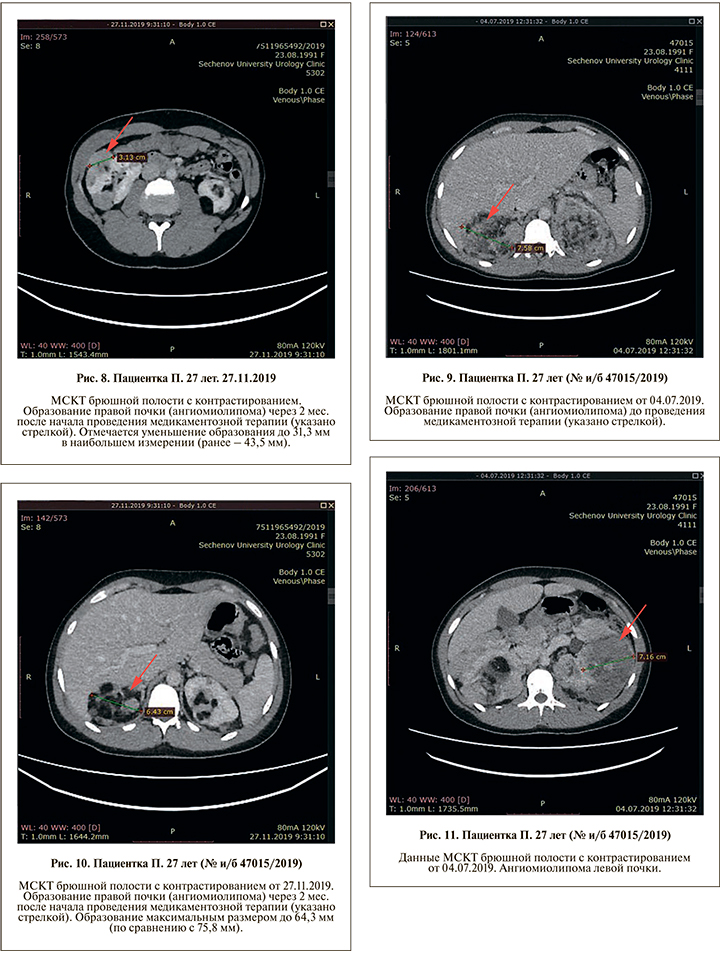

С октября 2019 г. пациентке проводится медикаментозная терапия препаратом эверолимус (Афинитор) 10 мг в сутки. Состояние пациентки удовлетворительное. По данным УЗИ и МСКТ с контрастированием, через 2 мес. в передне-нижнем сегменте правой почки определяется ангиомиолипома максимальным размером 31,3 мм (первоначальный размер образования – 43,5 мм) (рис 7, 8). В верхнем сегменте правой почки визуализируется объемное образование до 64,3 мм (ранее максимальный размер составлял 75,8 мм) (рис. 9, 10). Обращает внимание уменьшение преимущественно мягкотканного компонента. В заднем сегменте левой почки также отмечено уменьшение образования и гематомы: 38,4 по сравнению с 71,6 мм (рис. 11, 12).